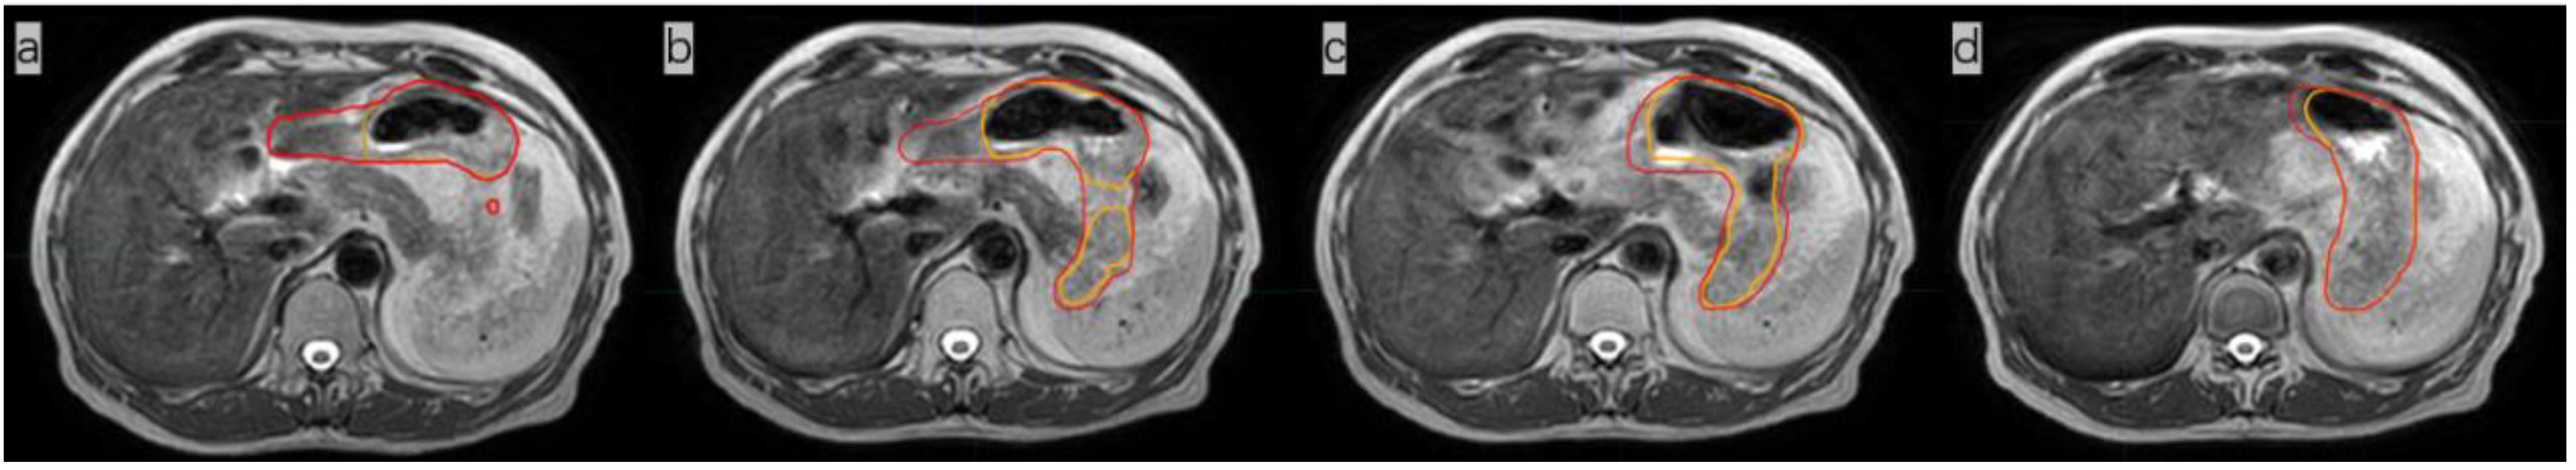

Figure 2.

Comparison of images of the whole stomach on the same plane after the 1st, 5th, 10th, and 15th fractions, showing the radiation oncologist’s delineation (red line) and the delineation obtained with AI (orange line). The dice similarity coefficient (DSC) of the three-dimensional stomach images indicated by these four outlines are 0.8311 (a), 0.9185 (b), 0.9193 (c), and 0.9427 (d), respectively.